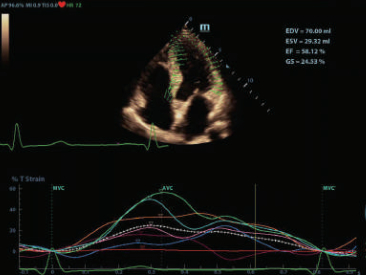

–Θ–Μ―¨―²―Ä–Α–Μ–Β–≥–Κ–Η–Ι –Η –≤―΄―¹–Ψ–Κ–Ψ–Ω–Μ–Ψ―²–Ϋ―΄–Ι –Ψ–±―ä–Β–Φ–Ϋ―΄–Ι –¥–Α―²―΅–Η–Κ –Ψ–±–Β―¹–Ω–Β―΅–Η–≤–Α–Β―² –Ω―Ä–Β–≤–Ψ―¹―Ö–Ψ–¥–Ϋ–Ψ–Β –Κ–Α―΅–Β―¹―²–≤–Ψ –≤–Η–Ζ―É–Α–Μ–Η–Ζ–Α―Ü–Η–Η –≤ –Α–Κ―É―à–Β―Ä―¹―²–≤–Β –≤ ―Ä–Β–Ε–Η–Φ–Α―Ö 2D, –Π–î–ö, 3D/4D –¥–Μ―è –±–Ψ–Μ―¨―à–Β–Ι –¥–Η–Α–≥–Ϋ–Ψ―¹―²–Η―΅–Β―¹–Κ–Ψ–Ι ―É–≤–Β―Ä–Β–Ϋ–Ϋ–Ψ―¹―²–Η –Η –Ω–Ψ–≤―΄―à–Β–Ϋ–Η―è –Κ–Α―΅–Β―¹―²–≤–Α –Η―¹―¹–Μ–Β–¥–Ψ–≤–Α–Ϋ–Η―è;